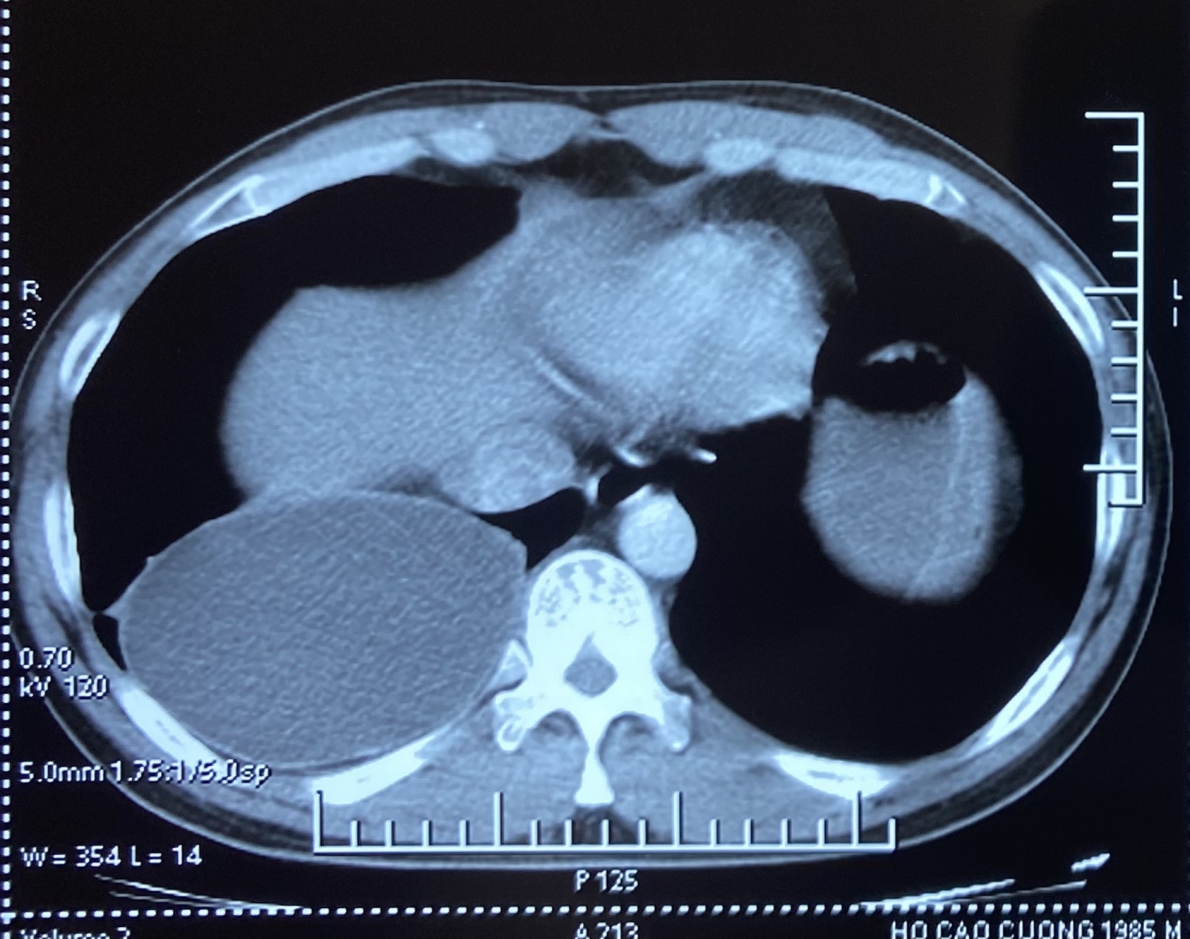

Sau khi khám, kết quả chụp phim CLVT lồng ngực cho thấy: tổn thương dạng nang thùy dưới phổi phải kích thước 12x9x8cm. Bệnh nhân được chỉ định phẫu thuật cắt nang dịch.

Tổn thương trên phim cắt lớp vi tính lồng ngực.